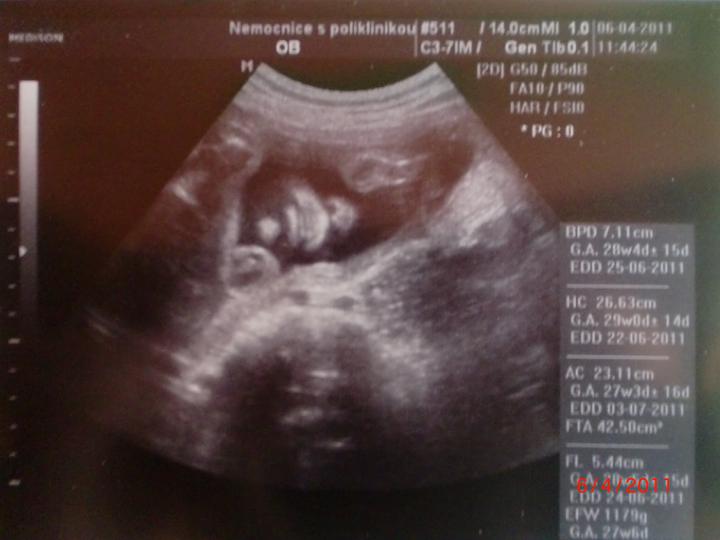

Doktor mi začátkem listopadu 2007 vysadil HA z důvodu zdravotních potíží,dávali jsme si tedy pozor a čekali,zda potíže ustoupí,ale 31.prosince 2007 mi manža řekl,že by chtěl miminko,byla jsem z jeho návrhu vykulená,ale byla to překrásná představa a tak jsem souhlasila..Od 8.ledna 2008 jsme se tedy začali snažit o miminko,začala jsem pít kontryhel a zobat Calibrum babyplan,aby mému tělu nic nechybělo 🙂 Nechávali jsme tomu volný průběh,ani jeden z nás na to nijak nepospíchal,nevím,proč jsem si říkala : Do roka se to snad povede 😀 A 29.3.2008 jsem měla pozitivní testík,sama jsem nechápala,jak brzy se to povedlo 🙂 Byla jsem neskutečně šťastná a stále jsem 🙂 Termín porodu dle MS 5.12.2008 a dle utz ve 12.tt 30.11.2008 Už od začátku jsem tušila,že čekám kluka a tak hned z první kontroly v 5.tt jsem si koupila modré bačkůrky pro štěstí,které se mnou chodili na každou kontrolu 🙂 Od 15.tt mi začalo celkem hodně tvrdnout břicho a chvilkama to bylo velice nepříjemné,na další kontrole,to jsem byla 18+4 , jsem to doktorovi řekla,ten mi pověděl,že se mu to vůbec nelíbí a tak mě poslal na utz,na utz jsem čekala 2 hodiny a můžu říct,že to byli nejhorší 2 hodiny v mém životě,tolik jsem se o miminko bála,ten strach,že něco není v pořádku byl opravdu k nevydržení..Přišla na mě řada a tak jsem tedy šla do kabinky a následně na lehátko na utz,pan doktor konstatoval,že všechno vypadá v pořádku a že se nemám bát,předepsal mi magnezium a že by to mělo pomoct,navíc koukám na ten utz a povídám panu doktorovi,to co tam vidím jsou kouličky? 😀 A on že jistě,že si myslel,že už to dávno vim,když se tak krásně ukazuje 😀 ,můj doktor mi řekl,že zřejmě porodím předčasně,což mě celkem vyvedlo z míry..Ale jsem optimisticky naladěnej človíček a tak jsem Honzíkovi vysvětlovala,že v bříšku musí ještě zůstat..Ve 20.tt jsem šla na velkej UTZ,kde mi opravdu řekli,že Honzík je zdravej a opět Honzík ukázal,že je 100% chlapeček 😀 Ve 26.tt jsme jeli na 4D utz do Liberce,tam se Honzík ukázal zas,no za celé těhu se nestalo,že by se na utz neukázal aa neroztáhl nožičky,máme malýho exibouše 😀 Ve 30.tt mě čekal další UTZ,vše v pořádku,Honzík už byl hlavičkou dolů a vážil 1600g ..Ve 35.tt mě doktor opět kvůli tvrdnutí břicha poslal už do ambulance,aby se o mě starali už tam.. Ten den jsem strávila v nemocnici 7hodin,fakt děsný !!! 2 hodiny čekání u mého doktora,ten mě tedy poslal už do nemocnice,takže jsem musela na UTZ,tam jsem čekala 2 hodiny,pak na natáčky,tam jsem čekala hodinu a pak na ambulanci a tak jsem čekala zas dvě hodiny ☹ Na UTZ ve 36.tt měl Honzík už 2600g ..